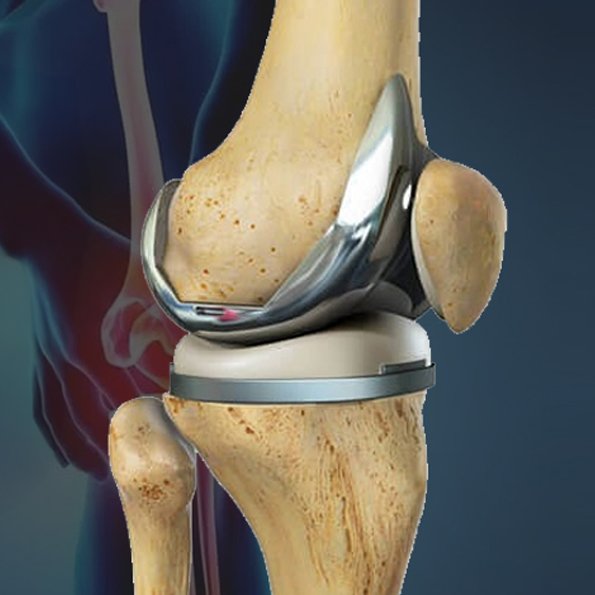

Our best knee replacement surgeon in Ahmedabad removes the injured bone and cartilage in the knee including the ends of the thigh and shin bones. An artificial joint in the form of a good knee is then substituted on the worn out surface. The implant consists of a robust metal and medical plastic and it functions as a new smooth joint and prevents the rubbing of bones against the bone. This surgery is aimed at restoring the functioning of your knee to enable you to lead a life free of pain.

This is a procedure that replaces your three compartments of your damaged knee joint. It is the best to use with advanced, extensive arthritis, as it can give total pain treatment and restore the range of motion by resurfacing the entire joint with long-lasting artificial implants.